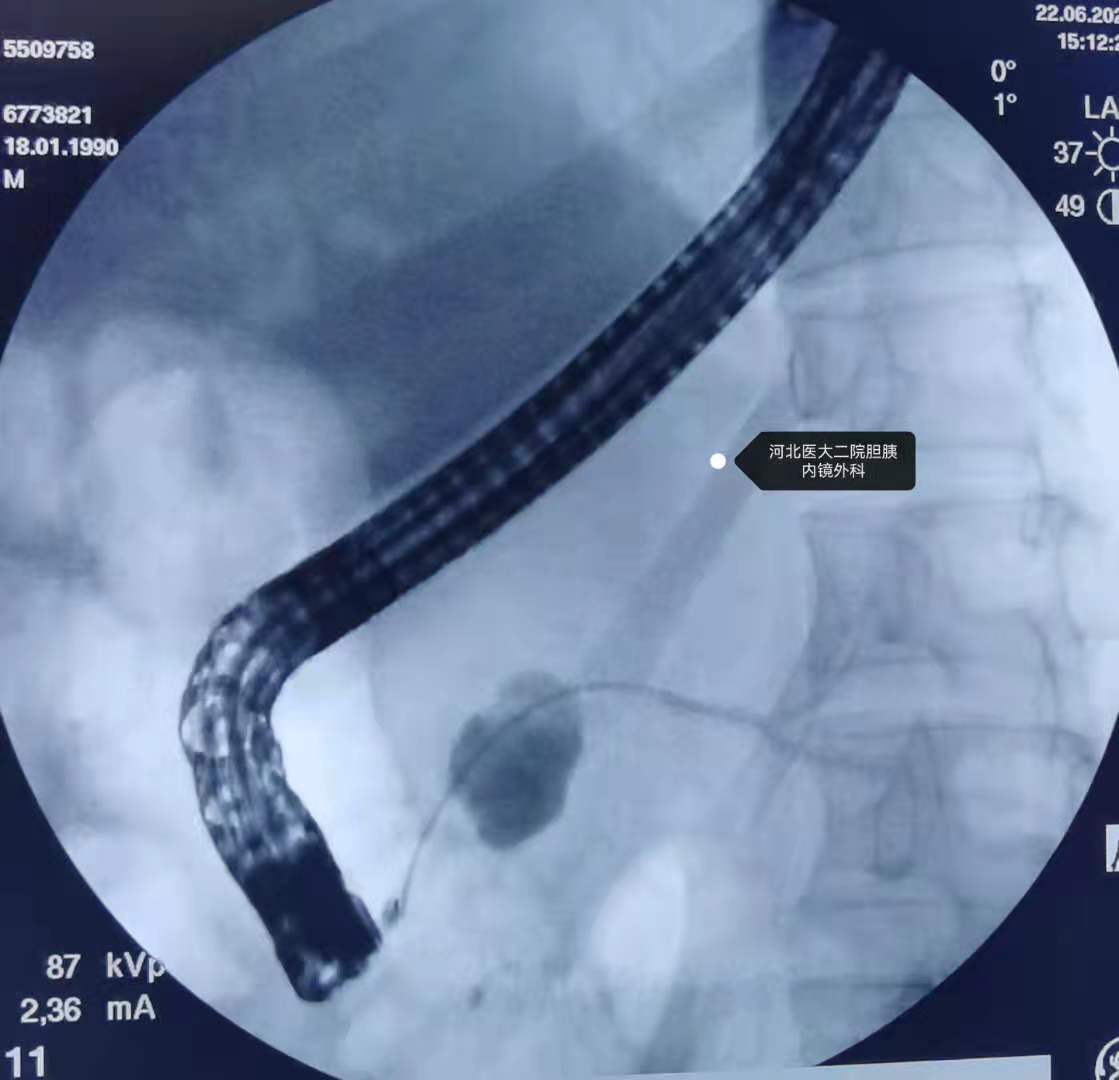

ERCP,主乳头插管。

导丝自腹侧胰管可进入残余胆总管内,但切开刀不能跟进。

考虑结石不能取出,决定置入胰管支架,但由于腹侧胰管狭窄,切开刀及导丝不能进入远端胰管。

决定行副乳头插管。

造影。

副乳头置入胰管支架。